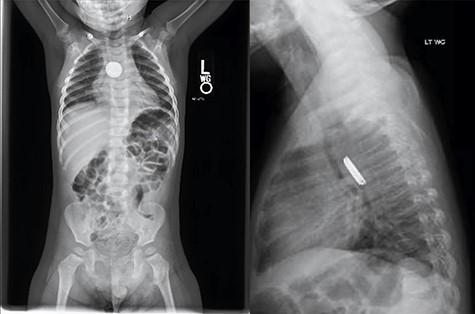

An 18-month-old male presented after his mother noted drooling, non-bilious emesis and a metallic smell to his breath which began 4 days prior. He was febrile to 102.5°F with 100% oxygen saturation on room air. Drooling was noted without stridor. Chest X-ray demonstrated a radiopaque foreign body with halo sign on anteroposterior and step-off on lateral view concerning for button battery (Fig. 1).

Chest X-ray demonstrated a radiopaque foreign body with halo sign on AP and step-off on lateral view concerning for button battery.